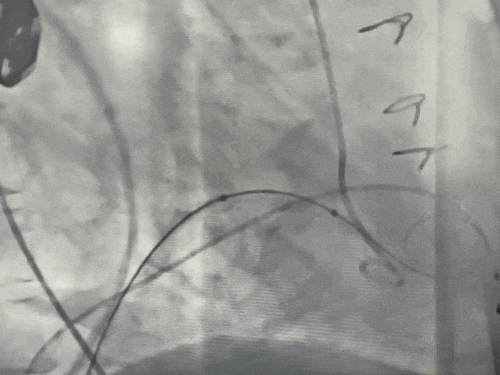

手术DSA

术前二尖瓣大量反流

球囊预扩张同时行左室造影评估